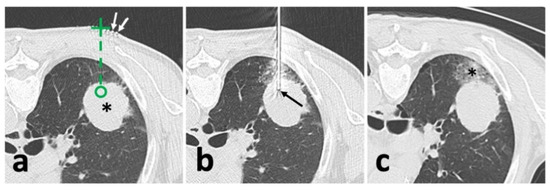

2.3. Conventional CT Guidance in Lung Biopsy

A 64-slice CT scanner (Philips Ingenuity Core128, Philips Medical Systems, Best, The Netherland) was used. The image acquisition parameters included: 120 kVp with adaptive current modulation, a pitch of 0.999, collimation of 64 × 0.625 mm, a gantry rotation time of 0.5 s, and a DoseRight index of 18. Axial CT images were reconstructed (slice thickness of 1.5 mm and increment of 1.5 mm) with iterative reconstruction (iDose level 5, Philips Healthcare). An initial scan was performed to establish the eligible puncture route to the target lesion under breath-holding after a full aspiration. After locating the target slice, the skin entry point was determined using the cross of a radiopaque grid placed on the patient skin and the perpendicular laser beam (Figure 1a) [2]. After dermal sterilization, draping, and local anesthesia, the patient was asked to hold the breath again, and a 17 G coaxial needle (Bard® TruGuide®, 17 G*13.8 cm, Bard Care, Covington, OH, USA) was advanced toward the target following the preset route and depth. Afterward, the chest CT was re-performed to check whether an eligible needle position was reached (Figure 1b). If not, the needle repositioning was carried out until the needle tip reached the target.

2.5. Lung Biopsy

After achieving an ideal position of the coaxial needle, the stylet was removed. Then, a biopsy instrument (Bard® Max-Core® Disposable Core Biopsy Instrument, 18 G*16 cm, Bard Care, Covington, OH, USA) was advanced to obtain samples (so-called “coaxial cutting needle technique”) (Figure 2e) [10,17,18]. Two to eight samples were obtained based on the pathological and other genetic test demands. Afterward, the needle was removed, and the post-biopsy CT or CBCT was routinely acquired to identify biopsy-related complications (Figure 1c and Figure 2f).

Figure 1. Illustration of conventional CT-guided biopsy. (a), localization with opaque grid marking (white arrow) and needle route planning (green dash line) targeting the solid lesion (*); (b), after needle puncture, CT showed an appropriate location of the needle tip (black arrow) within the solid lesion; (c), after removal of the needle and biopsy instrument, post-biopsy CT demonstrated pulmonary hemorrhage (*) alongside the puncture route without the findings of pneumothorax.